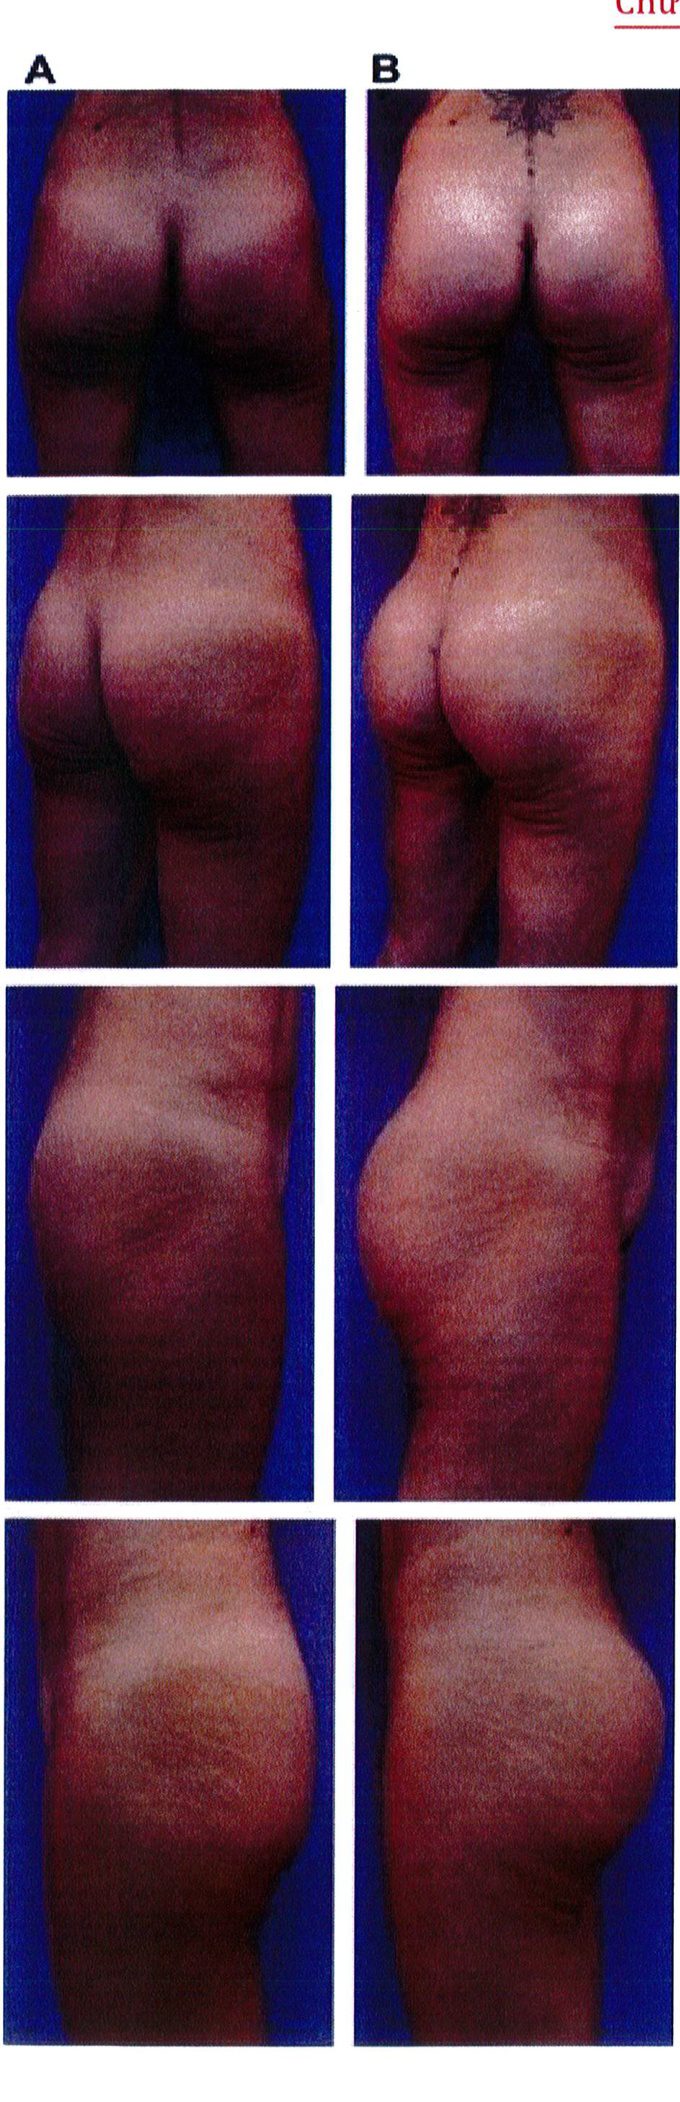

Hình. 18.. (A) Hình anh trước và (B) và sau phẫu thuật làm đầy mông của bệnh nhân được đặt khối implant dưới cân thể tích 225 mL, hai bên.

Hình. 18. (tiếp)

Bệnh nhân 31 tuổi tiền sử khỏe mạnh, có chỉ định nâng mông bằng implant do thiếu hụt thể tích. Hai khối anatomic implant 225 mL polyurethane dạng gel được đặt ở vị trí dưới cân. Sau phẫu thuật không ghi nhận biến chứng trong suốt quá trình hồi phục, vết mổ liền tốt (Hình 18).